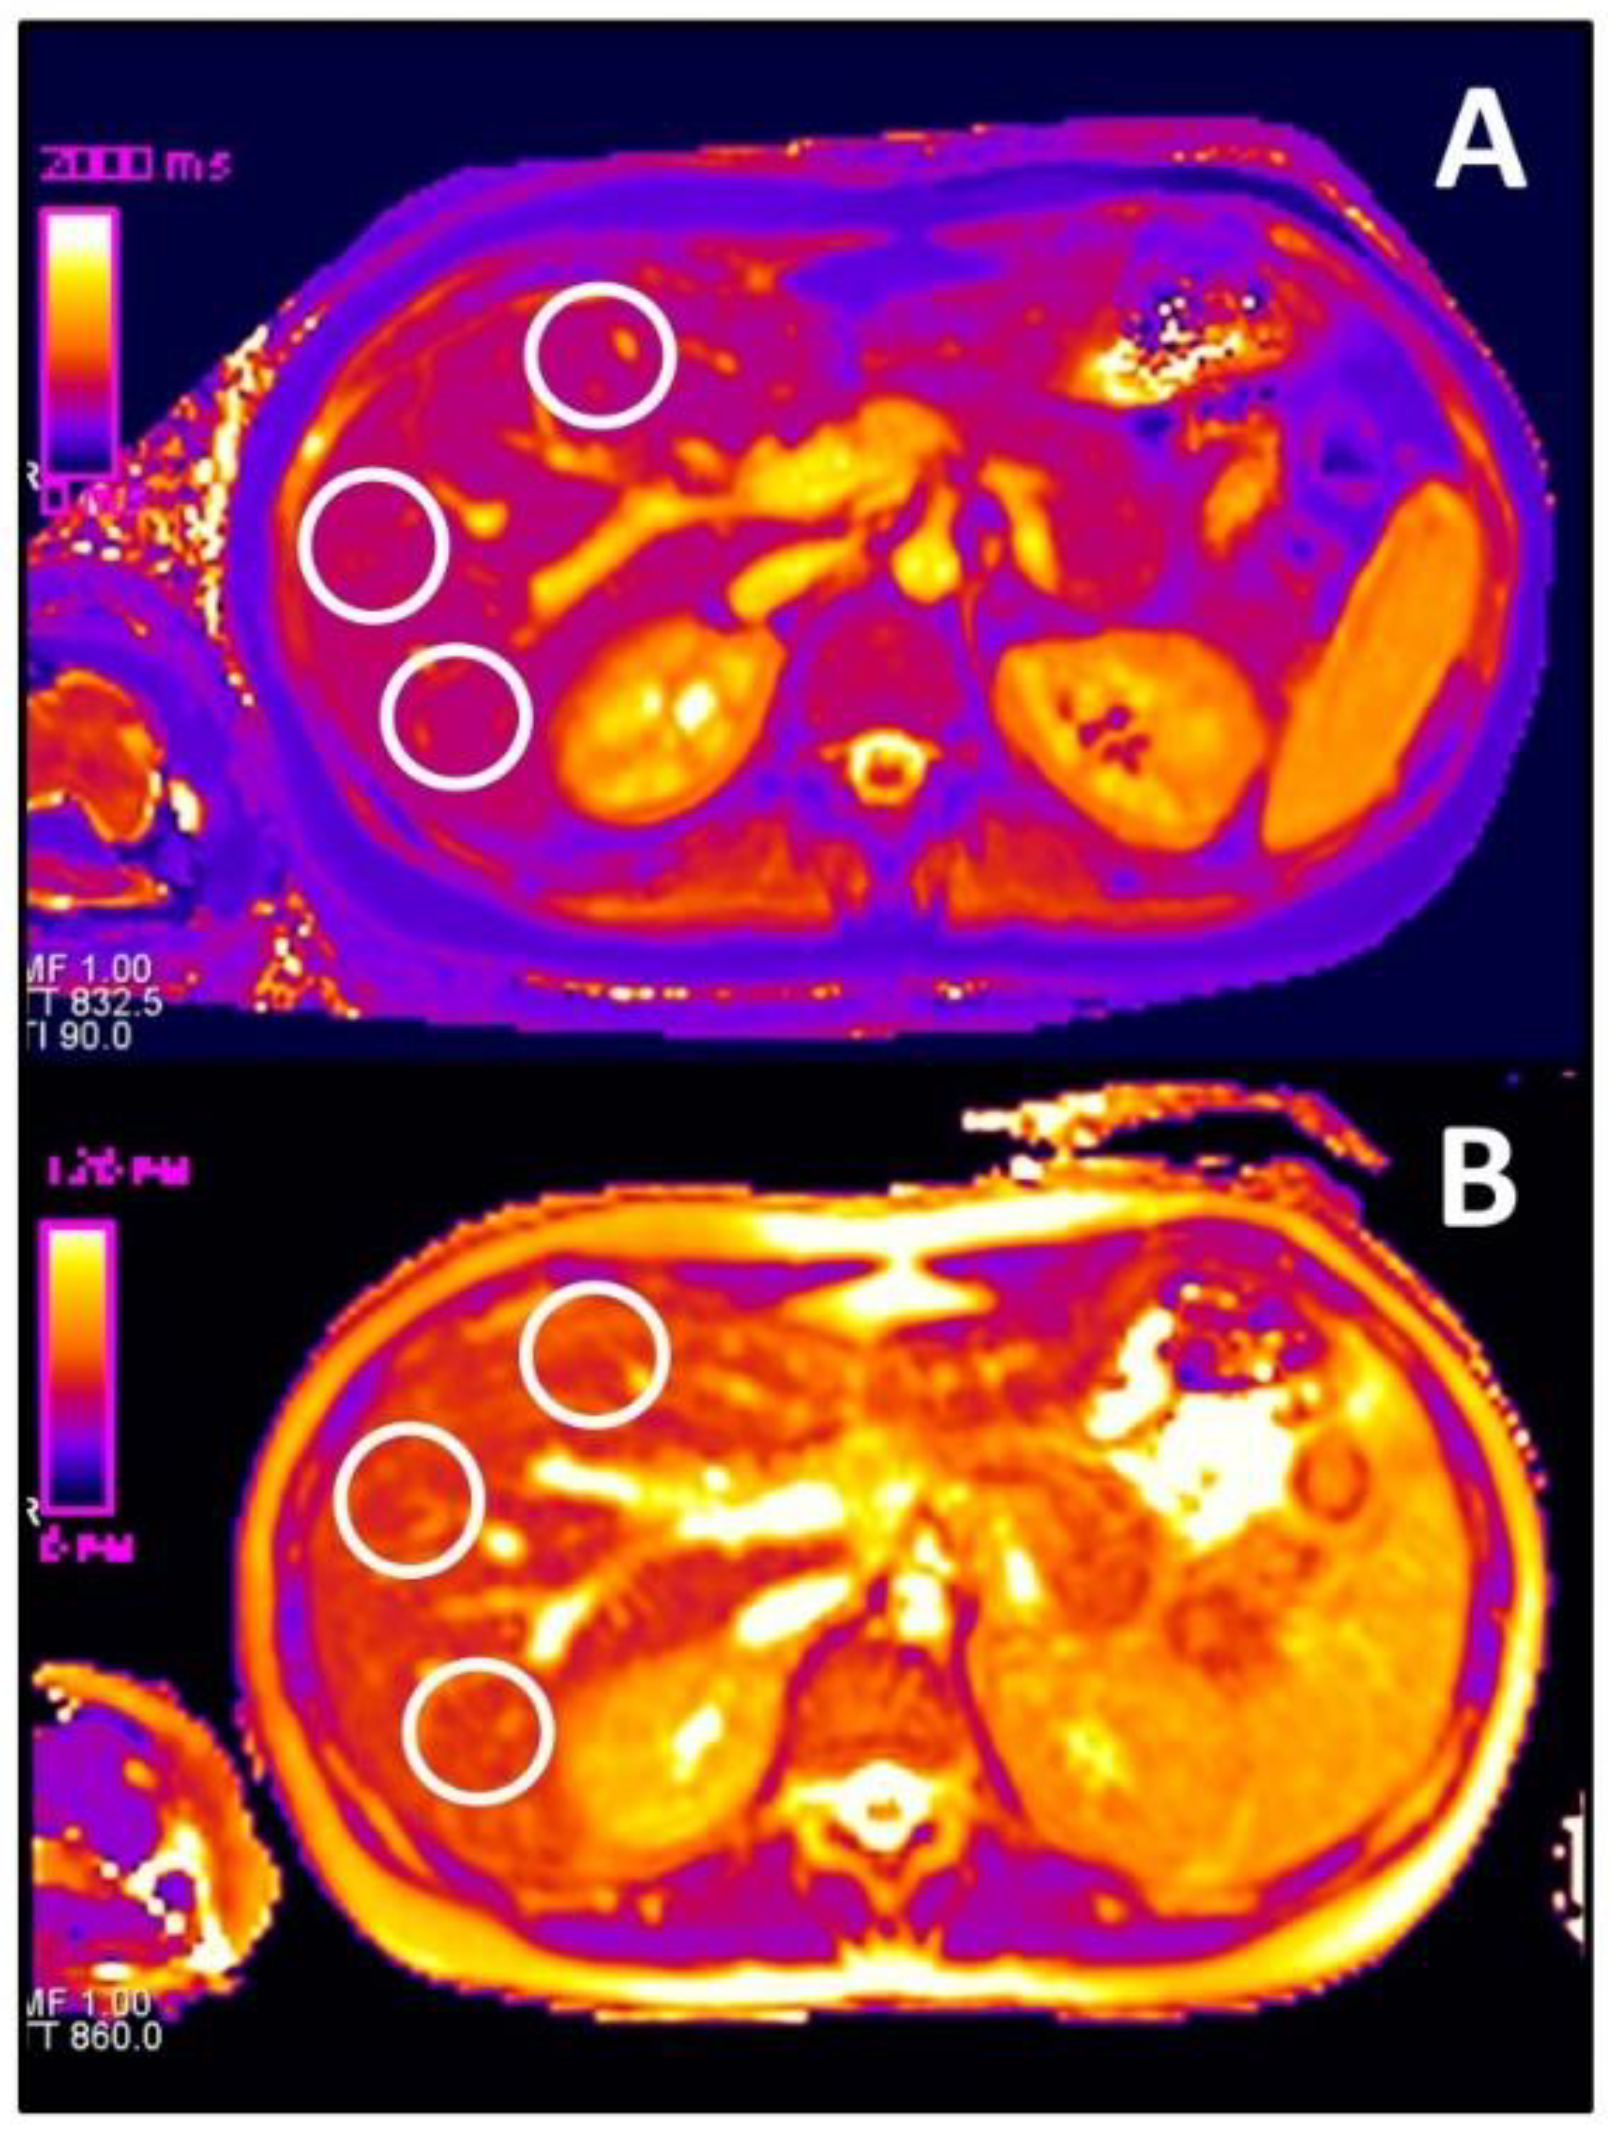

2.4. Image Analysis

2.4.1. T1 and T2 Relaxometry